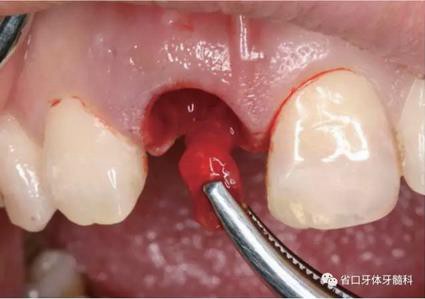

圖10 唇側(cè)骨壁完整

(1)微創(chuàng)拔牙及即刻種植:術(shù)前拍攝口內(nèi)照及實(shí)施牙周基礎(chǔ)治療。常 規(guī)消毒鋪巾阿替卡因局麻下微創(chuàng)拔除上頜右側(cè)中切牙,搔刮拔牙窩及根尖肉 芽組織。探測(cè)牙槽骨唇側(cè)骨壁及鄰面牙槽嵴完整,牙齦無(wú)撕裂。不翻瓣下于上頜右側(cè)中切牙缺隙近遠(yuǎn)中中點(diǎn)的腭側(cè)牙槽骨及根方定位,按照逐級(jí)預(yù)備的原則,緊貼牙槽窩腭側(cè)骨壁制備種植窩洞,植入Zimer®3.7mm×13mm TSV種植體1顆,植入扭矩>35N·cm,以O(shè)sstell測(cè)量種植體的ISQ值為68。 種植體平臺(tái)位于唇側(cè)齦緣中點(diǎn)下3mm,與唇側(cè)骨壁內(nèi)側(cè)面形成的跳躍間 隙約2mm,置入Bio-Oss®細(xì)顆粒骨粉0.25g,上愈合基臺(tái)關(guān)閉創(chuàng)口。術(shù)后 CBCT檢查顯示:種植體利用牙槽窩根方骨質(zhì)固位,緊貼牙槽窩腭側(cè)骨壁, 其唇側(cè)面與牙槽窩唇側(cè)骨壁的內(nèi)側(cè)面所形成的跳躍間隙(約2mm)可見(jiàn)顆 粒狀顯影物充填。牙槽窩的唇側(cè)骨壁及唇側(cè)倒凹無(wú)缺損穿孔。